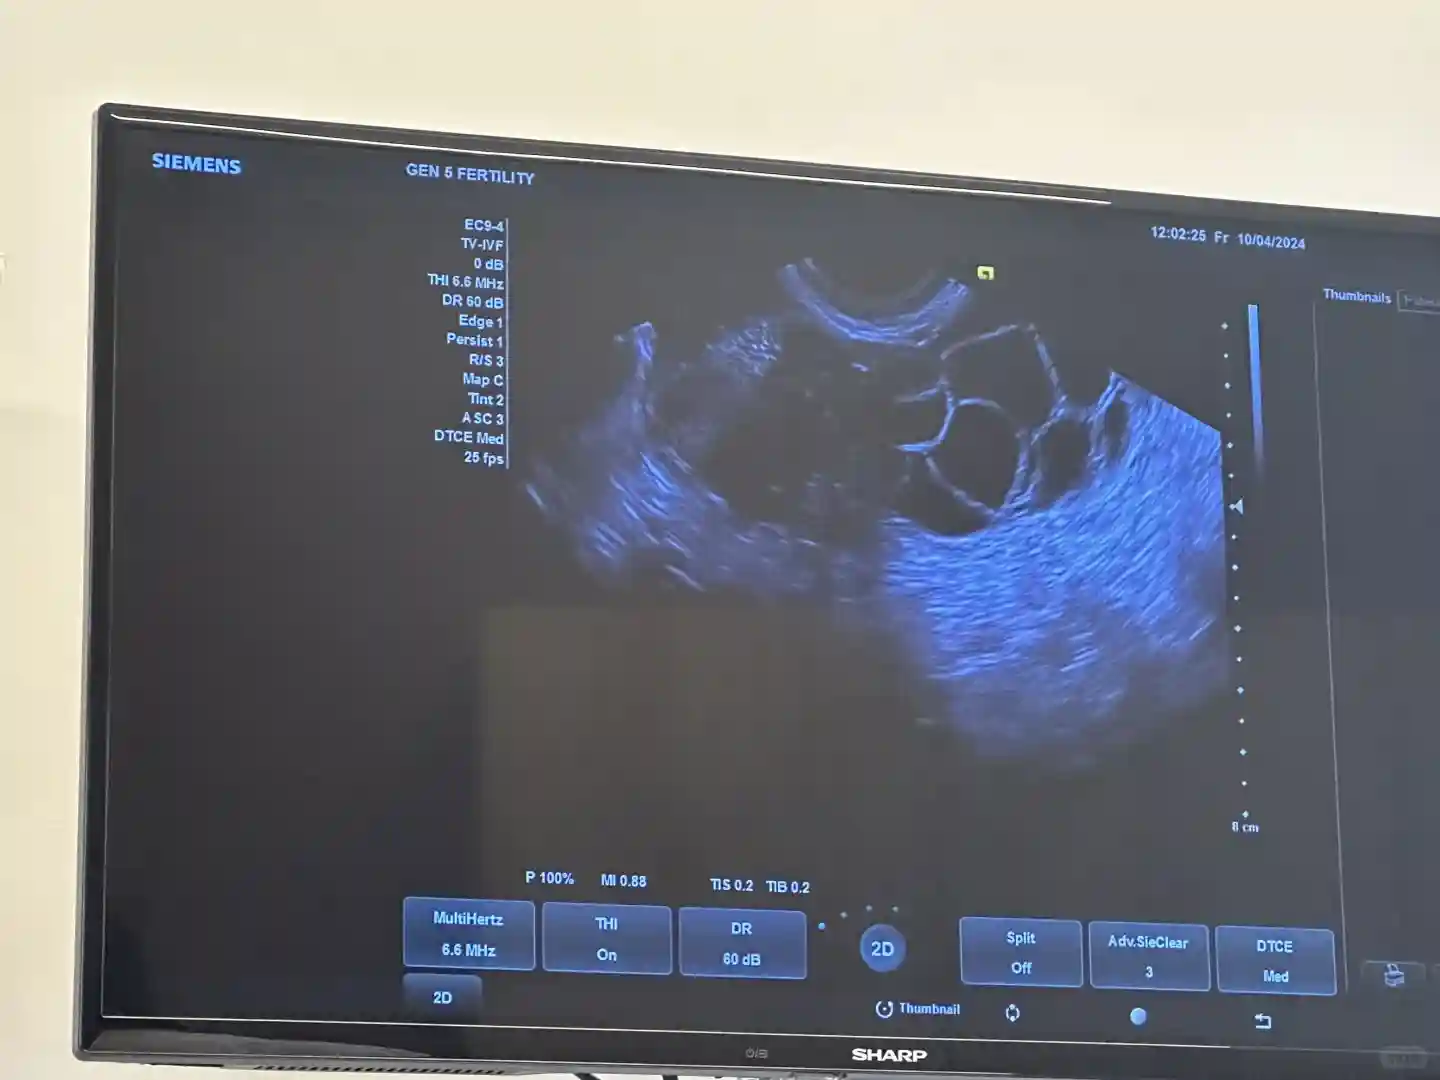

2024年8.24-9.17开始吃避孕药,然后开始打针,打两周左右 严格按照医生剂量来就好。5.取卵

2024.10.7号早上9:30取卵19颗(结果已出 见下篇)